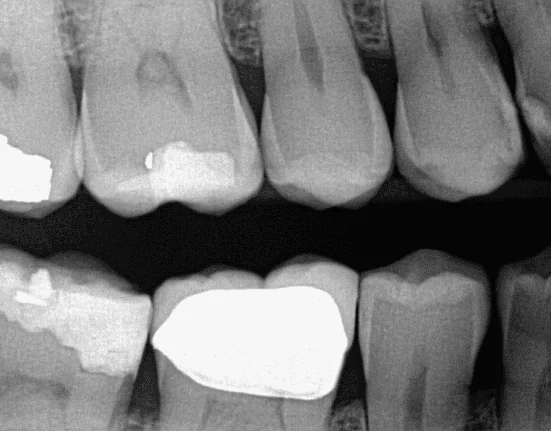

In this case, a 49-year-old male was examined during a routine dental exam. Teeth Nos. 28 and 29 displayed discoloration, possibly due to staining. Radiographs were taken, and there was no sign of cavitation (Figure 6). Prior to preparation, the ECD provided caries scores of 10 for tooth No. 28 and 11 for tooth No. 29 (Figure 7). After administration of local anesthesia, a 556 bur was used. Decay was detected, and the tooth was excavated and restored (Figure 8).